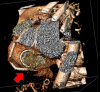

Case summary: The case of a 59-year-old man who underwent conservative mitral valve surgery with tricuspid valve annuloplasty is presented. The early post-operative period was complicated by acute coronary syndrome with inferior persistent ST-segment elevation. A coronary angiogram confirmed critical RCA hazy lesions, raising the suspicion of coronary kinking. To confirm the underlying mechanism for these lesions and determine the best treatment strategy, endocoronary imaging was performed, revealing coronary kinking of the RCA. Based on the persistent acute ischaemia, a long-lasting drug-eluting stent (DES) was implanted in the lower and upper knees of the RCA. After angioplasty, electrocardiography showed regression of the ST-segment elevation. Ten days later, coronary angiography and optical coherence tomography showed good results. The patient recovered from his myocardial infarction.